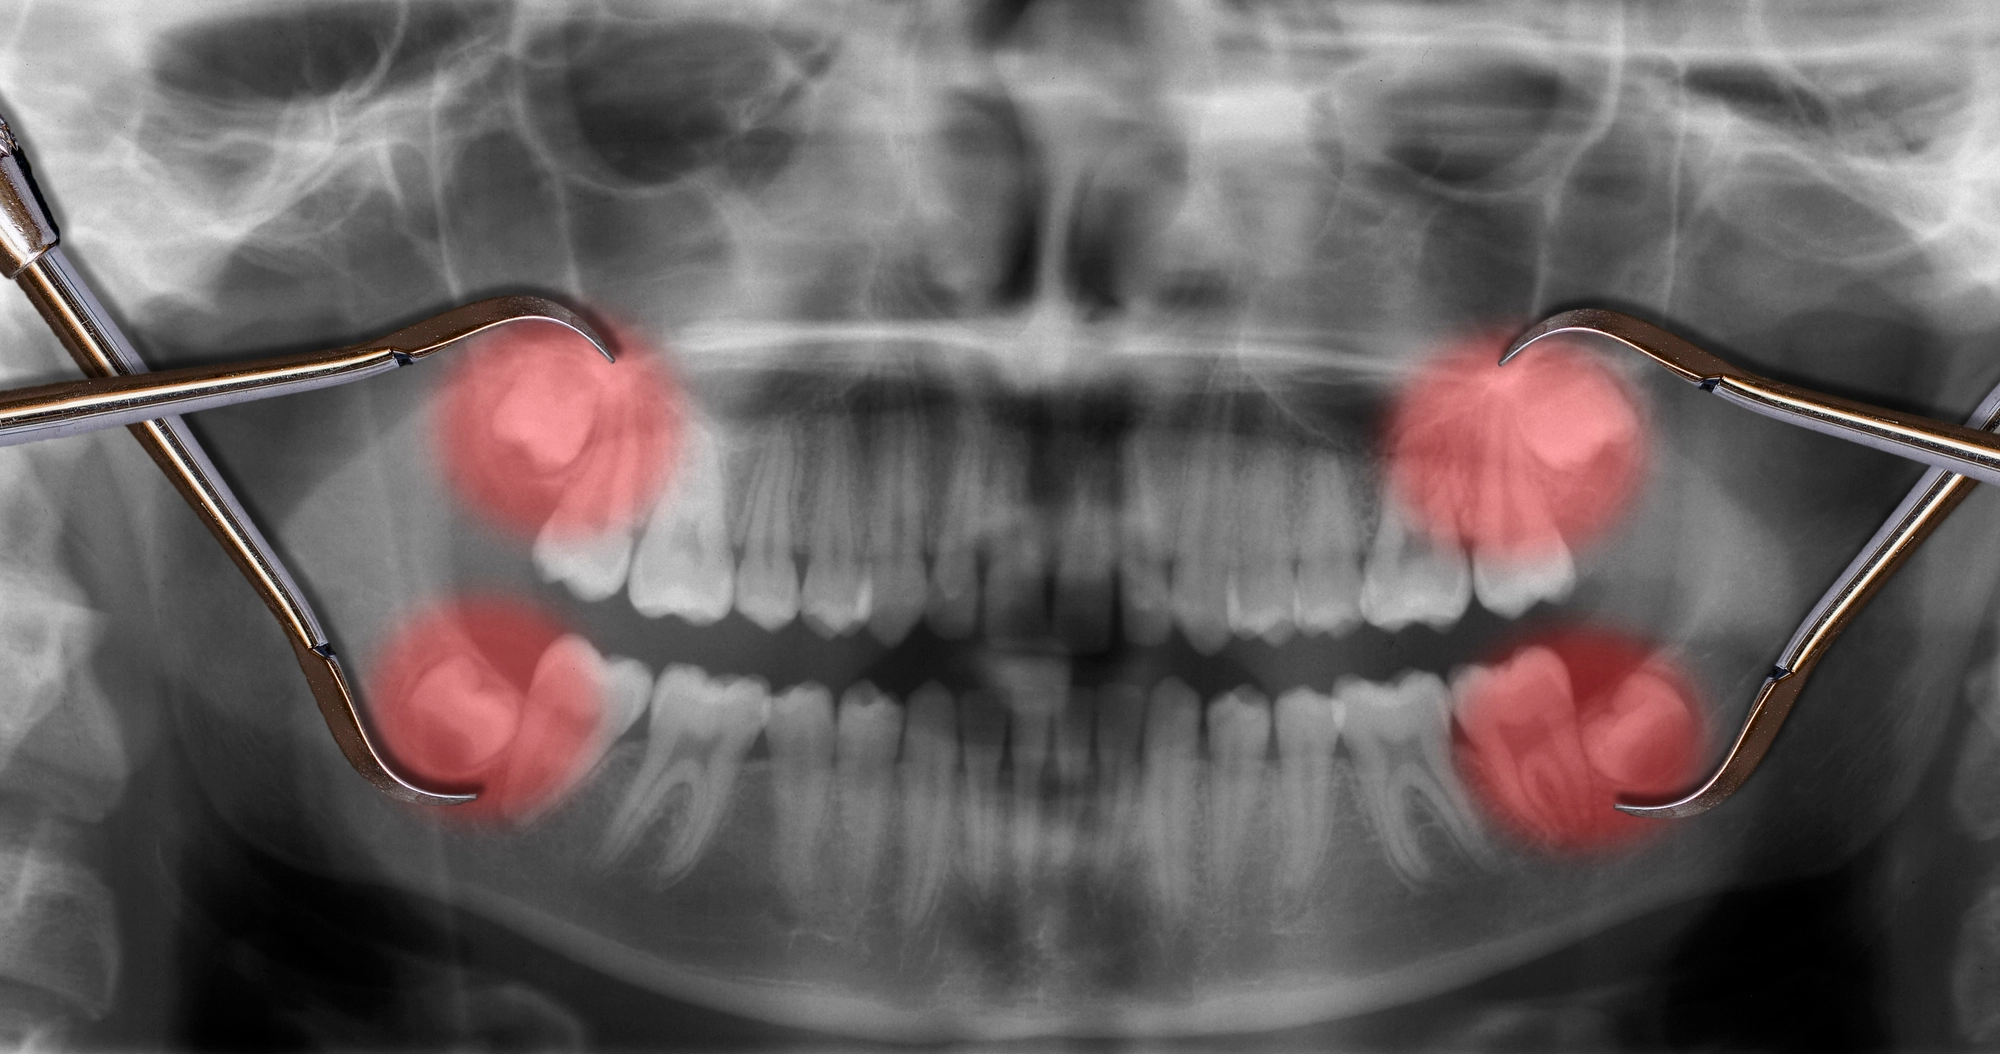

Wisdom teeth — the third molars that typically emerge in the late teens or early twenties — are a near-universal rite of passage, and not a pleasant one for most people. The human jaw has largely evolved to a size that simply doesn't accommodate a third set of molars comfortably, which means these teeth frequently cause problems whether they fully erupt or not.

Wisdom tooth extraction ranges from a straightforward in-office procedure for fully erupted teeth to a more involved surgical extraction for impacted cases. Sedation options are available and widely used — most patients have little to no memory of the procedure itself and are back home resting the same day. Recovery typically involves a few days of soft foods, some swelling, and diligent care of the extraction sites to prevent dry socket.

The earlier wisdom teeth are addressed, the simpler the process tends to be. Younger patients generally have less developed tooth roots, which makes extraction more straightforward and recovery faster.